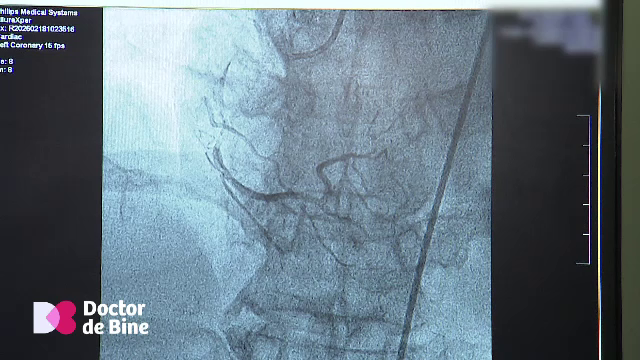

Cum se formează rețeaua naturală de „bypass” a inimii și creierului și rolul mișcării în protecția cardiovasculară

Colateralele sau „rețeaua de rezervă” a inimii ne pot salva viața.

Cum prin doar 30 de minute de mișcare zilnică se produc vase noi de sânge

Cât ne mișcăm în fiecare zi putem afla prin monitorizarea vaselor de sânge. Vorbim despre protecția ...